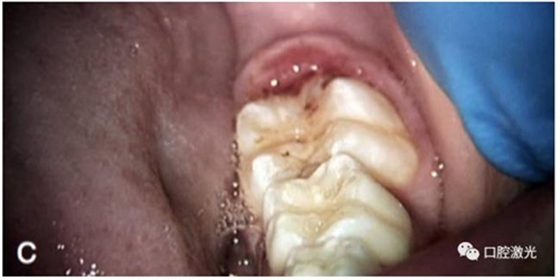

術(shù)后即刻